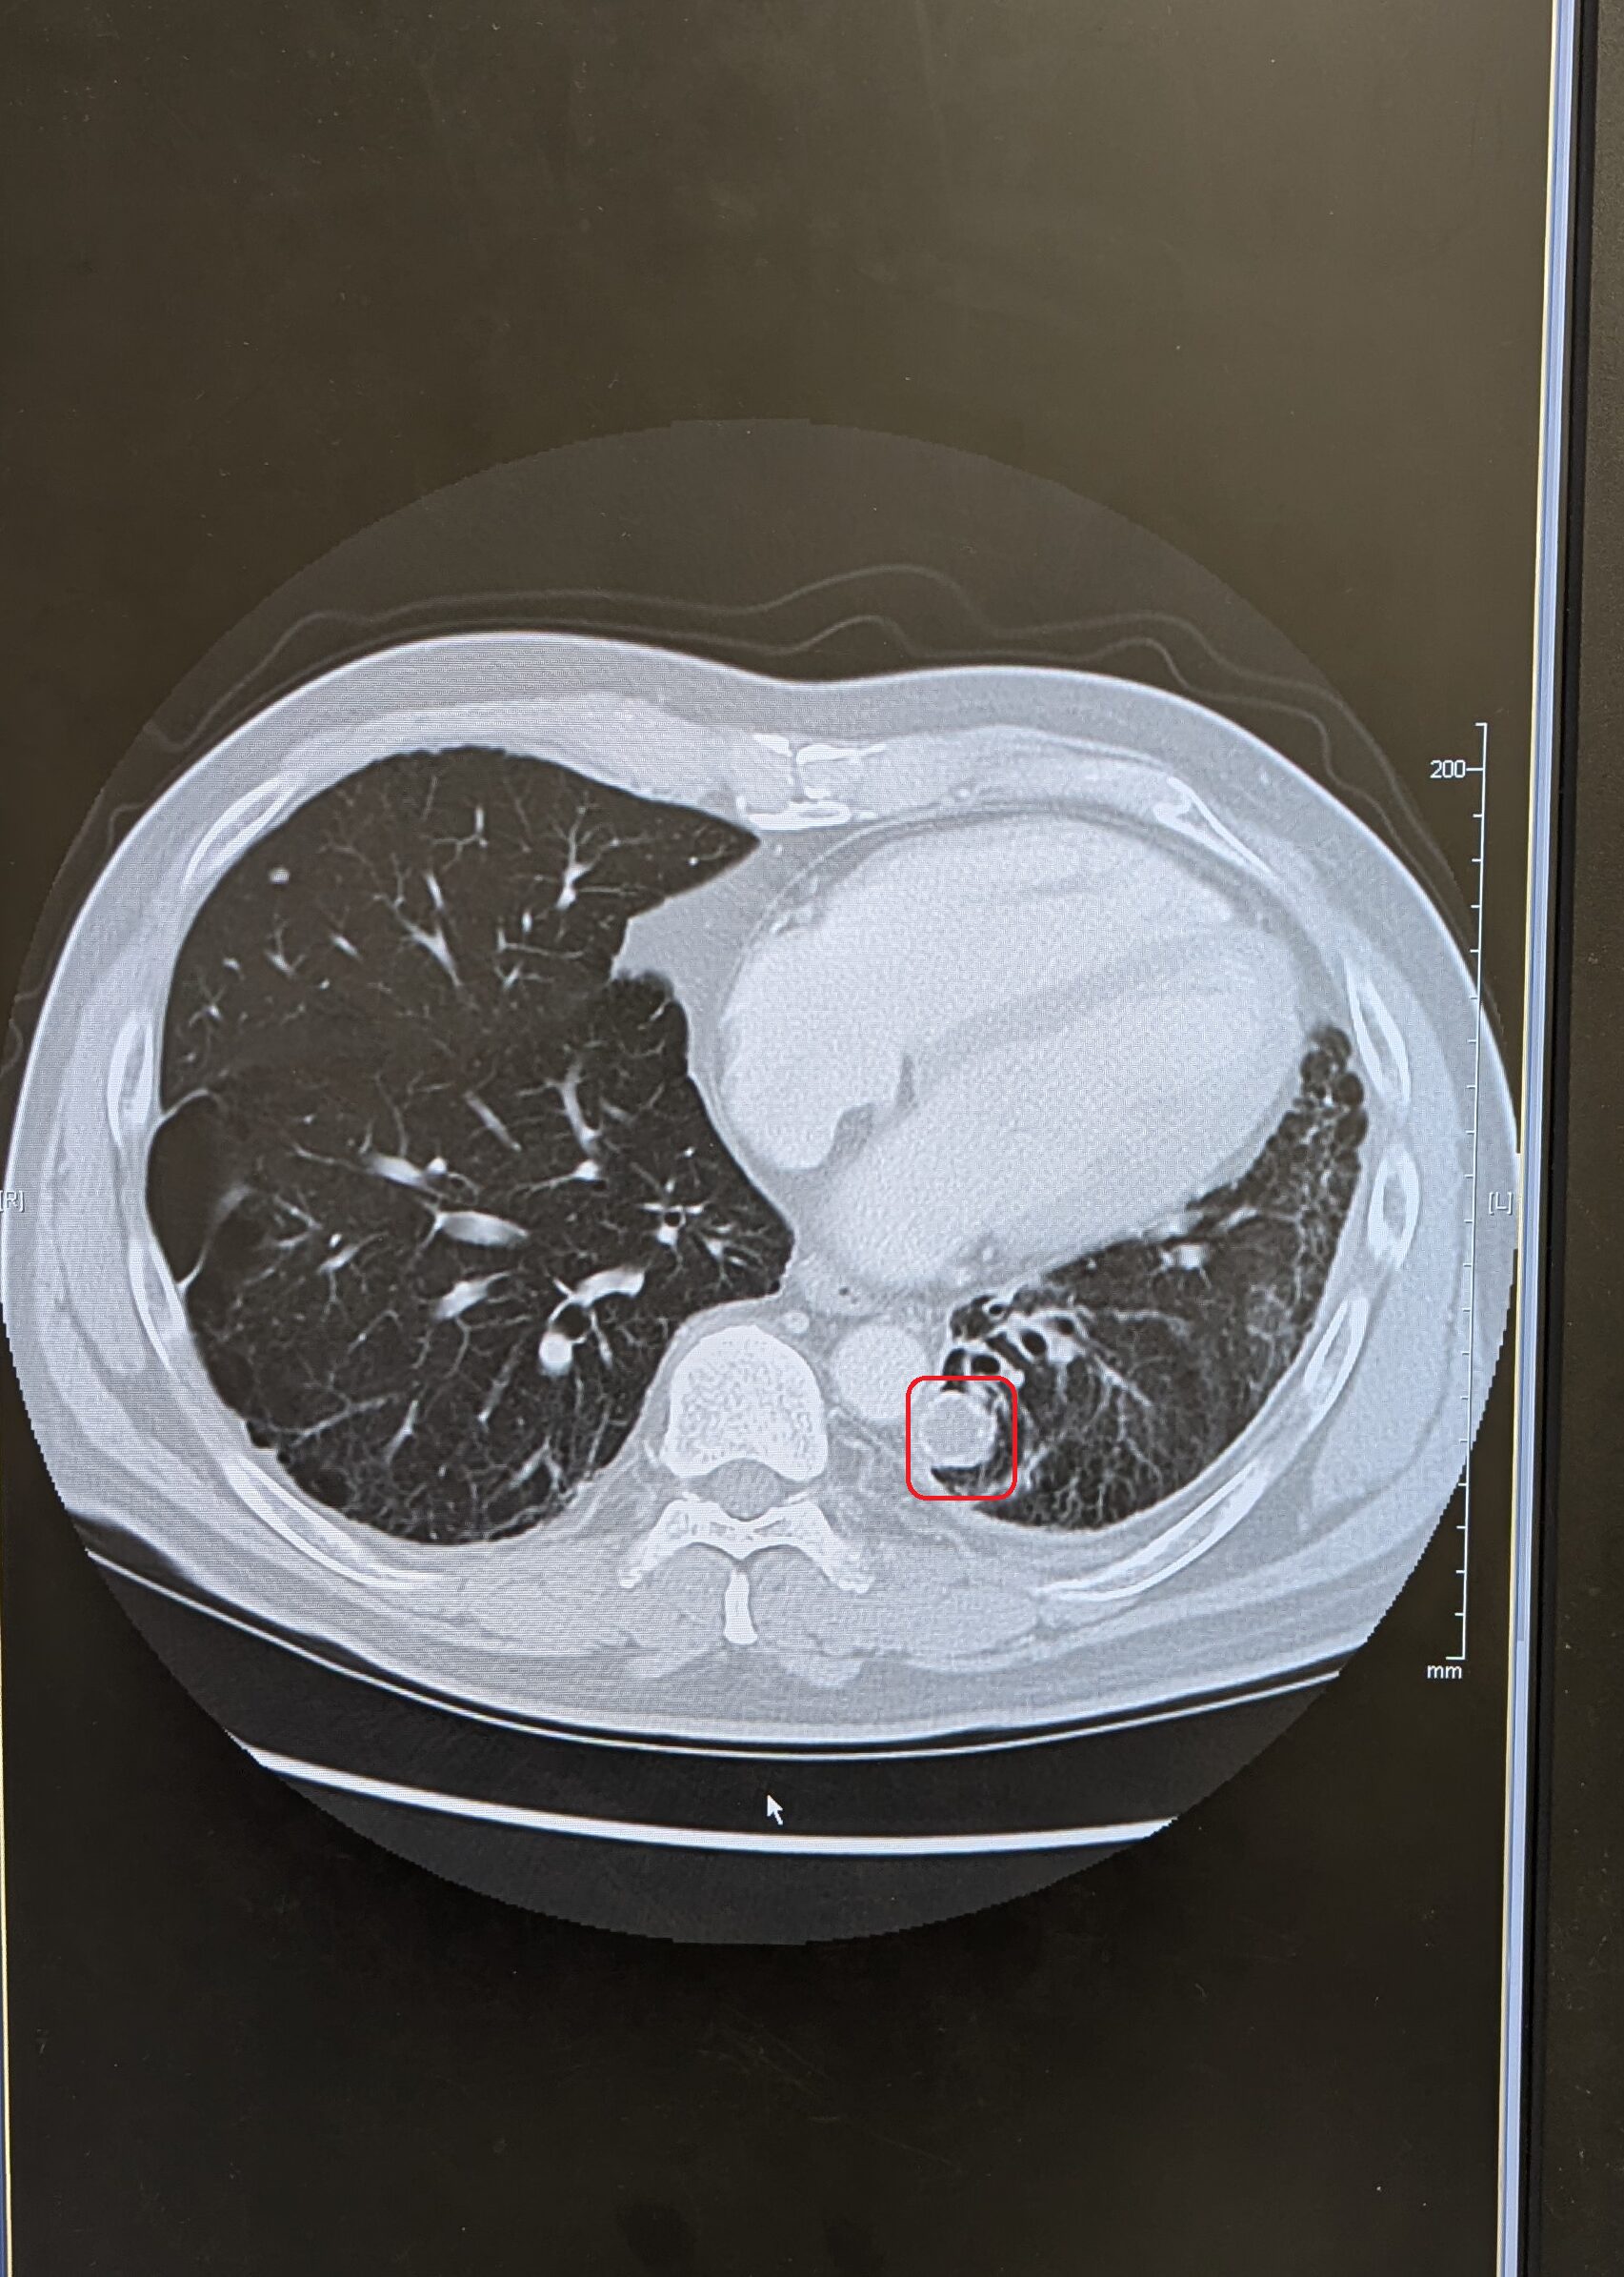

下記は今日撮ったCT

僕が「消えない」と言った部分は赤丸の部分・・・!

もう1年近くこの状態ですわ!

★CTやレントゲンは方向が逆になります!